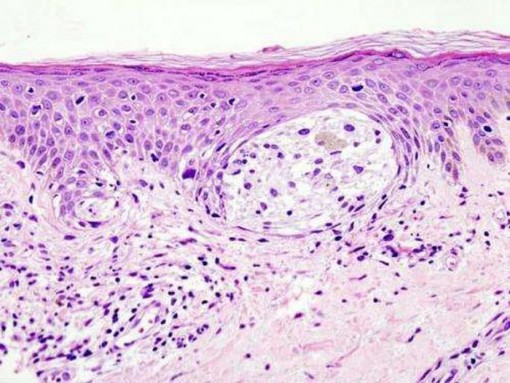

Bệnh da liễu bùng phát trong mùa nắng nóng, bác sĩ khuyến cáo cách phòng bệnh

Ghi nhận tại Bệnh viện Da liễu Trung ương, số lượng bệnh nhân đến khám da liễu trong thời điểm này có xu hướng tăng nhanh, đặc biệt là các bệnh liên quan đến nhiễm nấm và viêm da.